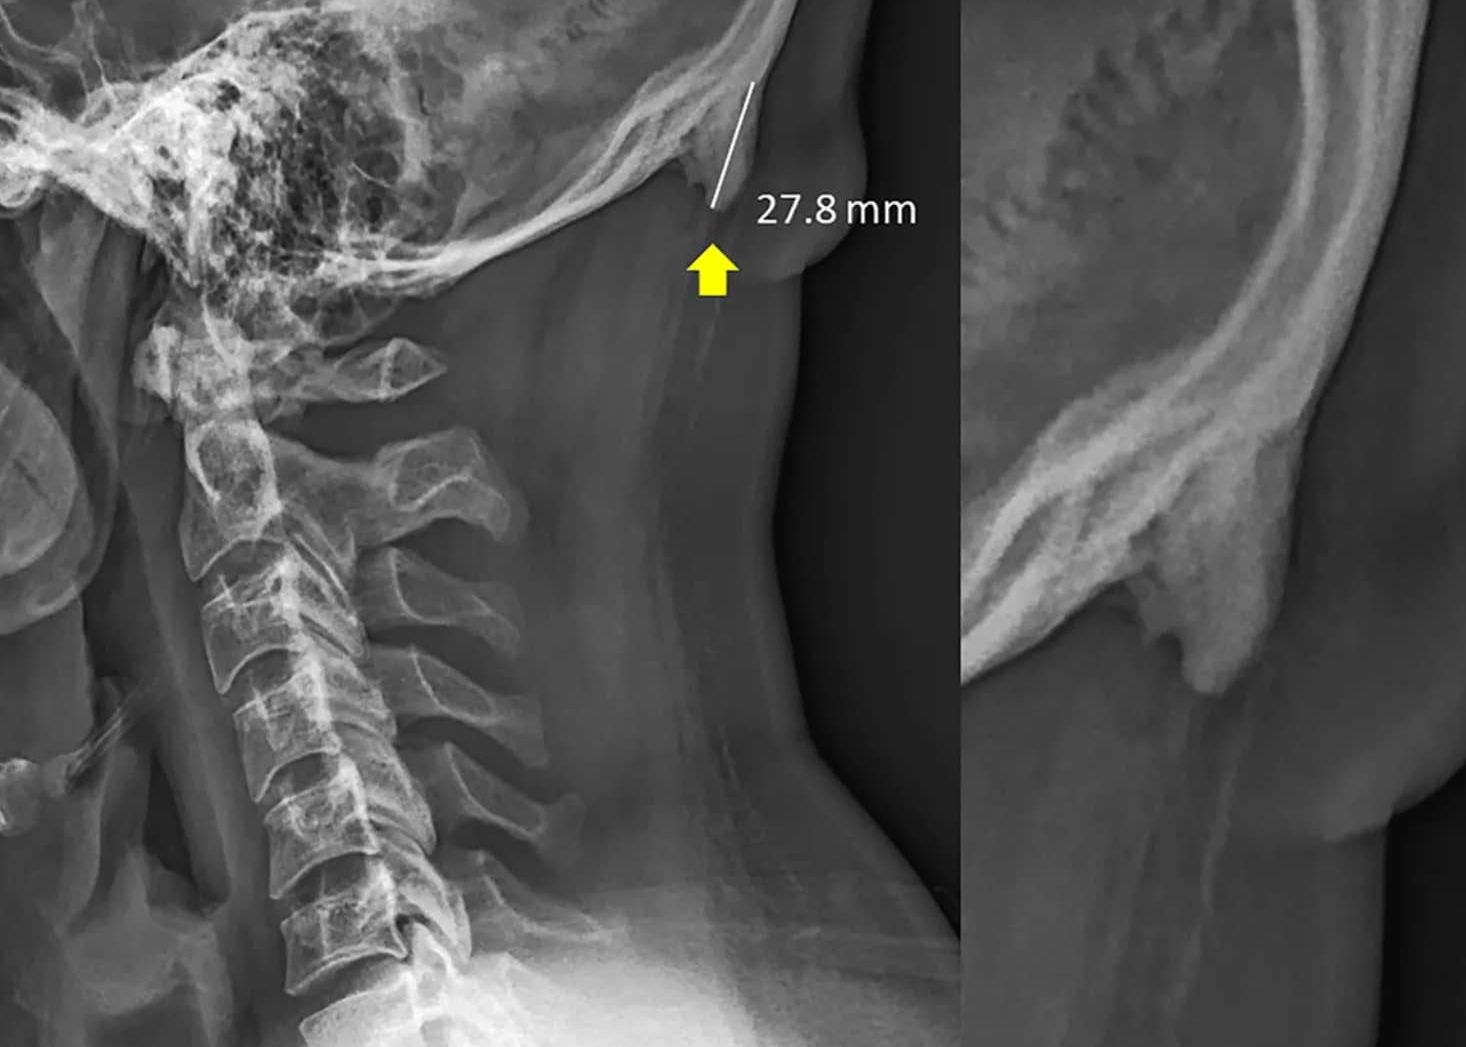

Mai exact, din cauza poziției înclinate a capului când este utilizat un telefon mobil, în spatele craniului au fost identificate două proeminențe, ca două coarne.

Mai multe studii despre acest fenomen au fost publicate începând cu anul 2016 și au avut la bază peste 200 de radiografii ale unor persoane aflate la vârste între 18 și 30 de ani. În 41% din cazuri au fost observate aceste probleme.